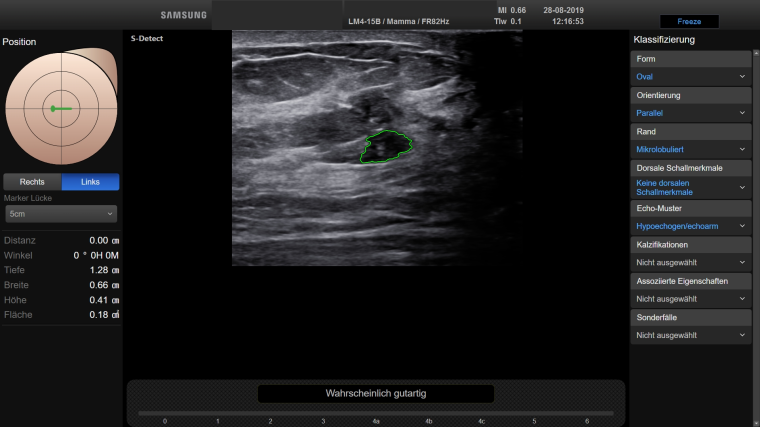

Duda: Während auf mammografischer Seite schon lange CAD-Systeme (Computer Aided Diagnosis) im Gebrauch sind, schien auf dem Gebiet des handgeführten Ultraschalls eine Unterstützung durch KI-Systeme (virtuelle oder künstliche Intelligenz) lange Zeit unrealistisch. Mit der jetzt verfügbaren Funktion des S-Detect im RS85 Ultraschallsystem der Firma Samsung können aber unklare Befunde im Sonogramm automatisch analysiert werden. Das Programm zeigt ohne Vorgabe des Untersuchers verfügbare Umrisse und macht Vorschläge zur Beschreibung und zur Dignitätseinstufung (Abb. 1 und 2). Diese Zusatzfunktion ist sekundenschnell verfügbar und gibt dem Untersucher eine zusätzliche Sicherheit bei schwierigen Befunden, aber beispielsweise auch bei Therapiekontrollen.